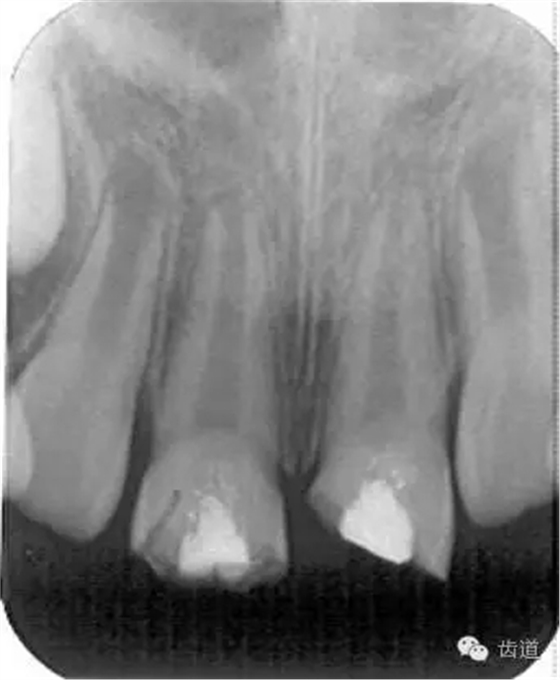

3個(gè)月左右在X線片上可觀察到修復(fù)性牙本質(zhì)層的出現(xiàn), 術(shù)后6個(gè)月左右,常可觀察到連續(xù)的有一定厚度的修復(fù)性牙本質(zhì)層; 修復(fù)性牙本質(zhì)層的出現(xiàn),是間接牙髓治療成功的重要指征。

術(shù)后當(dāng)天

術(shù)后五個(gè)月